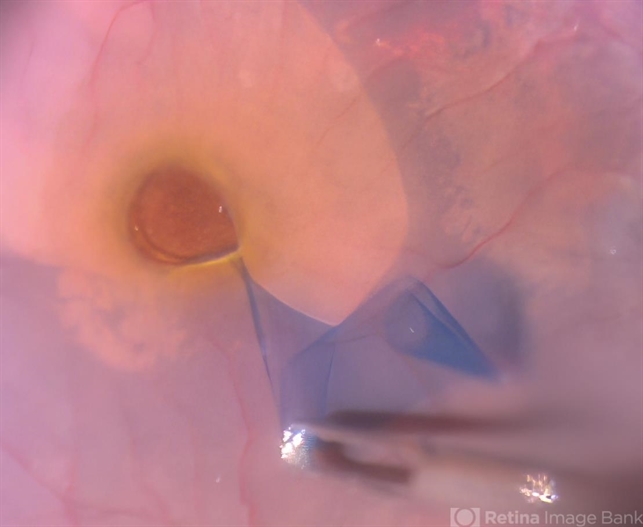

- internal limiting membrane (ILM) peeling, Macular hole

- An intra operative still showing a stained ILM removal done with forceps in case of large macular hole.